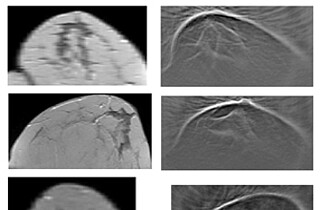

To detect tumors and visualize tissue structures, physicians use an imaging process, called Magnetic Resonance Imaging (MRI). In this process, contrast media are applied to better recognize structures and to distinguish tumors from healthy tissue.

KIT scientists of the Institute of Nanotechnology (INT) have developed an uncharged iron complex compound that resembles natural complexes in the body. The magnetic behavior of this complex depends on temperature. When used as a contrast medium, the temperature difference between the tumor and surrounding tissue is visualized much better. This additional contrast cannot be achieved when using known gadolinium complexes. Instead of the hazardous gadolinium, the new complex contains an iron atom as a central particle that is coordinated by two ligands. Electrostatic forces of attraction between the central particle and the ligands ensure stability in an aqueous environment. The location of the energy levels and, hence, the magnetic properties are influenced by ambient temperature.

The exact temperature at which switching from the non-magnetic to the magnetic behavior takes place can be adjusted by the selection of the organic ligands. Hence, the magnetic behavior may change at small temperature changes, such as that in the tumor tissue, already. This is then reflected by different relaxation times in the MRI. In addition, the complex compound may also be used for storage media, temperature sensors, or papers, the color of which varies depending on temperature.